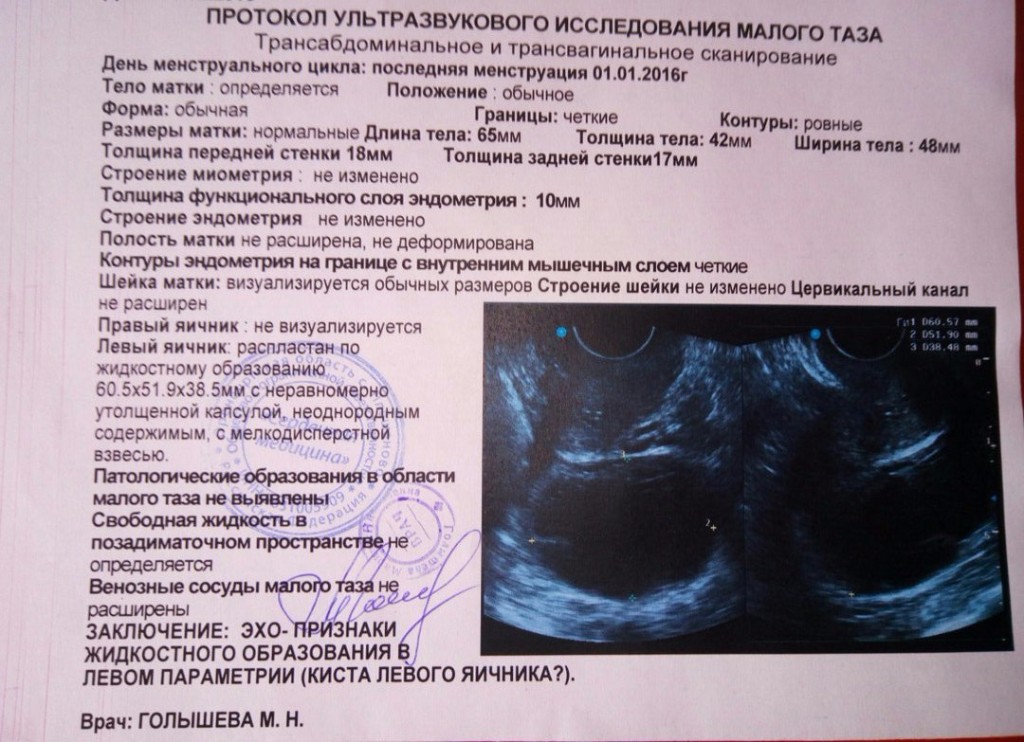

Анатомия женского организма: строение и функции матки

Раздел: Фотопуть к знанию